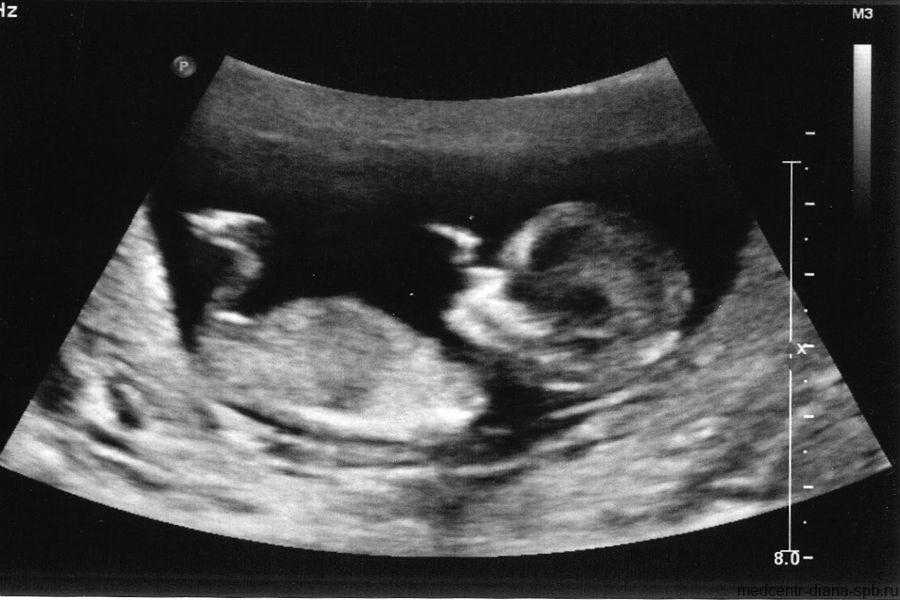

Фото УЗИ ребенка на 12 неделе беременности

Это очень важный период, поскольку гинеколог направляет женщину на первый скрининг. Он включает УЗИ и биохимический анализ венозной крови на гормоны. Ультразвуковое исследование в это время очень информативно и позволяет определить ряд врожденных патологий.

Визуально на фото видны такие особенности плода:

- хорошо просматриваются глаза (они обычно закрыты), нос малыша и другие черты лица;

- ребенок может открывать рот и глотать околоплодные воды;

- размеры плода все еще непропорциональны, но все части тела сформированы;

- в области половых органов происходит гипотрофия мошонки у мальчиков или гипертрофия половых губ у девочек (по этим признакам можно определить пол);

- движения плода хаотичные.

Скрининг на 12 неделе позволяет определить ряд патологий внутриутробного развития. Для этого аппарат УЗИ проводит ряд автоматизированных замеров. На основе этих измерений производят оценку формирования плода.

В этот период обязательно определяют такие параметры:

- длина плода;

- длина бедра;

- окружность живота;

- обхват головы;

- копчико-теменной размер (КТР) – длина от темечка до копчика;

- бипариетальный размер (БПР) – размер от одного виска до другого;

- толщина воротникового пространства;

- объем грудной клетки;

- вес плода (рассчитывается исходя из замеров).

Сопоставить эти данные и выявить патологию может только врач. Если специалист подозревает врожденное заболевание, назначают дополнительный хромосомный анализ.

Снимок УЗИ